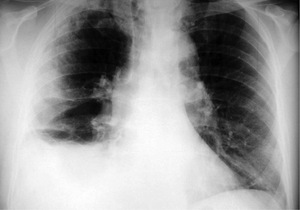

W EKG poza tachykardią i niepełnym blokiem prawej odnogi pęczka Hisa nie odnotowano innych nieprawidłowości. RTG klatki piersiowej w projekcji PA przedstawiono na rycinie 1.

2. RTG klatki piersiowej w projekcji PA (ryc. 1) przedstawia:

a) Cechy prawostronnego śródmiąższowego zapalenia płuc

b) Trójkątne zacienienie, mogące odpowiadać zawałowi płuca prawego

c) Płyn w prawej jamie opłucnowej

d) Wszystkie powyższe stwierdzenia są prawdziwe